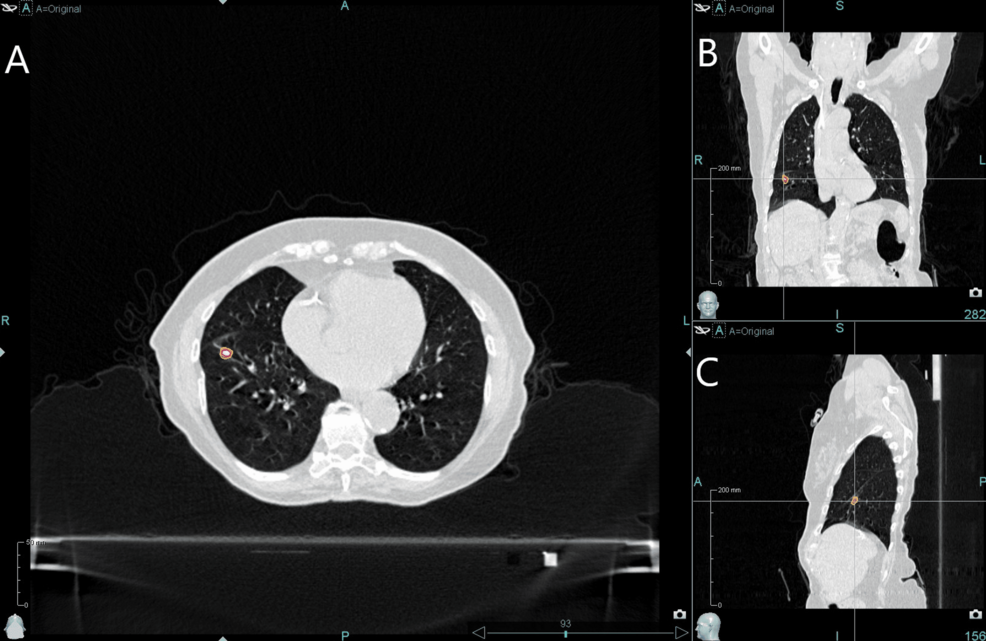

This case report explores the dosimetric impact of unmanaged intrafraction prostate motion during radiotherapy by retrospectively analyzing real-time motion data collected using the Radixact® System with Synchrony®. The study models what would have happened if a patient had been treated without motion management, using deformation vector fields to simulate dose